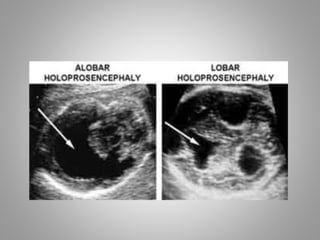

Types Of Holoprosencephaly

3 Types

Alobar

Cerebrum appears as single entity.

Semilobar

Partial attempt to form 2 hemispheres.

Lobar

2 hemispheres are formed but midline structure

is abnormal.

Usg Features

• Alobar and Semi-lobar types show absence of

falx and absent or non fused thalami.

• Alobar has 3 sub variants

1. Pan cake -Thin plate of cerebrum with large

dorsal Cyst

2. Cup - somewhat more tissue of cerebrum

with dorsal cyst

3. Ball – single mono-ventricle surrounded by

brain tissue of varied thickness.

Types Of Holoprosencephaly 3Types Alobar Cerebrum appears as single entity. Semilobar Partial attempt to form 2 hemispheres. Lobar 2 hemispheres are formed but midline structure is abnormal.

Usg Features • Alobarand Semi-lobar types show absence of falx and absent or non fused thalami. • Alobar has 3 sub variants 1. Pan cake -Thin plate of cerebrum with large dorsal Cyst 2. Cup - somewhat more tissue of cerebrum with dorsal cyst 3. Ball – single mono-ventricle surrounded by brain tissue of varied thickness.